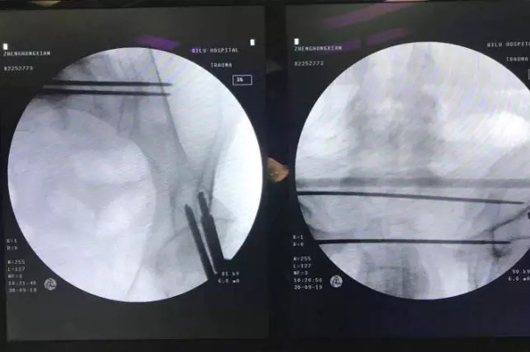

依托成熟的手术手艺,,,,,,并团结手术机械人在精准性、稳固性和可视化操作上的优势,,,,,,仅用时20分钟,,,,,,团队就完成了螺钉的精准植入。。。。。与古板的开放式手术相比,,,,,,此次手术创口更小,,,,,,极大地降低创伤,,,,,,镌汰术中出血,,,,,,并且有用加速了患者康复历程。。。。。

▲ 术前及术中妄想

▲ 导针及螺钉精准植入